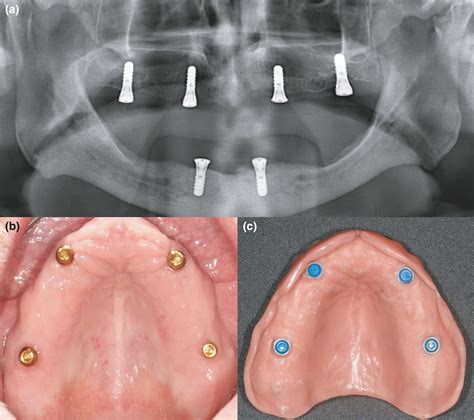

Over denture implants are a type of dental implant that supports a denture, providing a more secure fit compared to traditional dentures. These implants are surgically placed into the jawbone and act as anchors for the denture, preventing it from slipping or moving out of place. This stability enhances the overall comfort and functionality of the denture, allowing patients to enjoy their favorite foods and speak with confidence.

There are two main types of over denture implants: ball-retained and bar-retained.

• Ball-Retained Implants: These implants feature a ball-shaped attachment that fits into a corresponding socket on the denture. This design allows for easy attachment and removal of the denture.

• Bar-Retained Implants: These implants use a thin metal bar that is attached to the implants and fits into a corresponding attachment on the denture. This type provides a more stable fit and is often preferred for lower dentures.

The next step is the surgical placement of the implants. This procedure is usually performed under local anesthesia. The dentist will make small incisions in the gum tissue to expose the jawbone and then place the implants into the bone. The gums are then sutured closed, and the implants are allowed to heal and integrate with the bone over a period of several months.

Once the implants have fully integrated with the jawbone, the dentist will attach the denture to the implants. For ball-retained implants, the dentist will place the ball-shaped attachments onto the implants and fit the denture with corresponding sockets. For bar-retained implants, the dentist will attach a thin metal bar to the implants and fit the denture with a corresponding attachment.